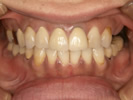

50代女性

前歯に義歯をしているが、話しづらく、インプラントを検討され来院されました。

前歯にインプラントを埋入。

食事もしやすくなり、話しやすくなったと喜んでいただけました。

![]() |

|

| 治療前 | |

| 治療後 | |